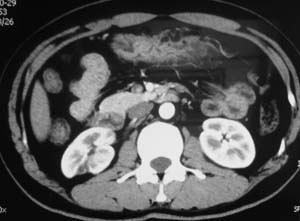

以下是引用子期在2010-3-19 20:47:00的发言:[br]血管畸形的ct增强应该有明显强化,本例并不相符合。本例双肾局部的略低密度影,累及肾盂,局部皮质明显变薄、内陷,增强扫描有轻度的强化,应考虑为炎性病变,患者为年轻男性,累及双肾的感染以结核较常见,可以没有明显的临床症状,尿中有时候也并不能查出什么;肾脓肿常有明显感染中毒症状,本例不符,另外一般的肾盂肾炎或肾小球肾炎通过小便就可确诊,其它还不能排除的是黄色肉芽肿性肾盂肾炎,然而单凭ct一般也很难鉴别。